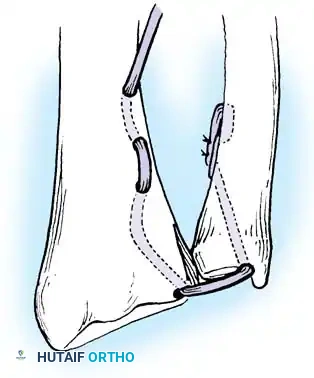

Preparation of the distal ulna: Drill holes are created at the fovea to facilitate transosseous suture passage for anatomic TFCC reattachment.

Transosseous Repair Technique:

1. Identify the foveal detachment arthroscopically or via an open dorsal ulnar approach.

2. Prepare the ulnar fovea down to bleeding bone using a burr or curette to stimulate a healing response.

3. Utilize a targeting guide to drill two converging osseous tunnels from the ulnar neck into the fovea.

Passing non-absorbable sutures through the osseous tunnels in the ulna to capture the peripheral edge of the TFCC.

- Pass strong, non-absorbable sutures (e.g., 2-0 FiberWire) through the TFCC using an outside-in or inside-out technique, then shuttle the suture limbs down the osseous tunnels.

The sutures are tied securely over the cortical bone bridge of the ulnar neck, restoring tension to the radioulnar ligaments.

- Tie the sutures over the ulnar cortical bridge with the forearm in neutral rotation to restore anatomic tension.